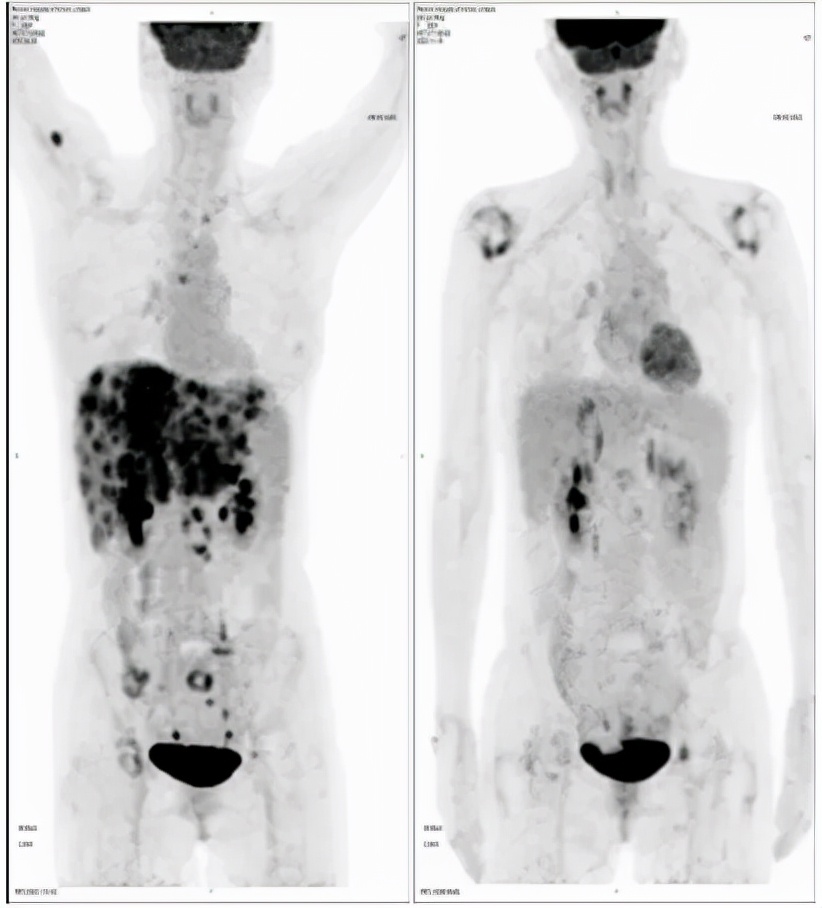

2020-11-15

2020-11-18PET-CT提示:1.胰腺体部结节,代谢增高;肝实质多发稍低密度团块、结节灶,代谢增高;全身多发骨质密度不均,代谢稍增高;上述考虑胰腺癌伴多发转移灶治疗后改变,少许活性尚存。2.左锁骨上区及胸廊入口处淋巴结,较前缩小,代谢减低;肝门区、胰腺周围及腹膜后区高代谢淋巴结未见明显显示;上述考虑转移灶经治疗后改变,活性受抑

2020-4-22 2020-11-18